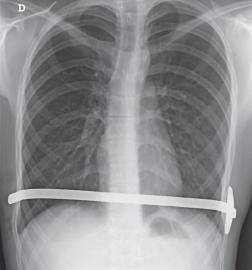

Imágenes y Cirugía

Natalia González Alcolea, María Dolores Chaparro Cabezas, Félix Martínez Arrieta, Victor Sánchez Turrión